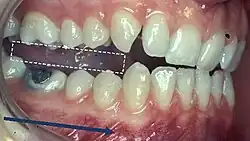

When describing the relationship between maxillary and mandibular incisors, the following categories make up Angle's incisal relationship classification:

- Class I: Mandibular incisors contact the maxillary incisors in the middle third or on the cingulum of the palatal surface

- Class II: Mandibular incisors contact the maxillary incisors on the palatal surface, in the gingival third or posterior to the cingulum. This class may be further subdivided into division I and division II:

- Class III: Mandibular incisors occlude with the maxillary incisors on the palatal surface, in the incisal third specifically or anterior to the cingulum

- In some cases the overjet is reversed (<0mm) and the mandibular incisors lie anterior to the maxillary incisors

5) Contacts in ICP

Begin by assessing the incisor and molar relationship as described above. Similarly examine the overbite and overjet. An overbite of 3-5mm[2] and an overjet of 2-3mms are considered to be within the range of normal.[13]